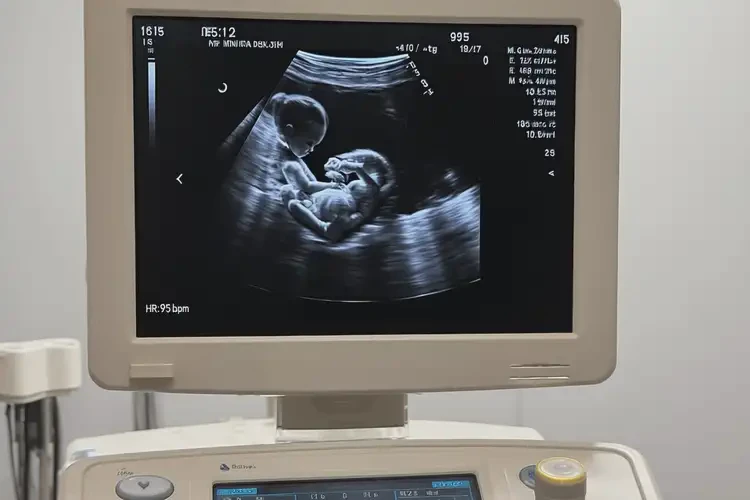

孕16周胎心95怎么回事

胎心95次/分鐘

孕16周時,胎心正常范圍通常在140-170次/分鐘。胎心95次/分鐘明顯低于正常值,可能提示胎兒存在某些問題,需要進一步檢查和評估。

孕16周胎心95怎么回事(圖1)